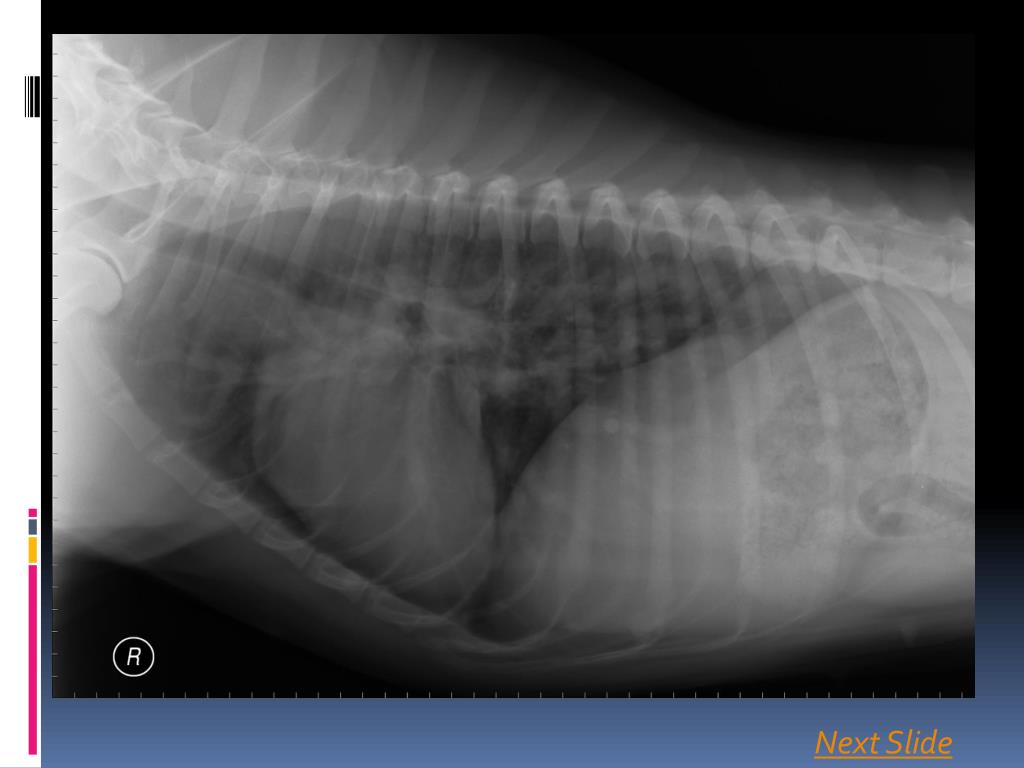

3. Signalment • Maggie Mae presents to your clinic with a 3 month history of progressive exercise intolerance and cough • On physical examination, you hear increased lung sounds • You order thoracic radiographs Next Slide

4. Next Slide

5. Next Slide

15. Correct! The cardiac silhouette is abnormal. Click on the selection below that correctly identifies the abnormal area. • The Left Ventricle • The Right Ventricle • The Left Atrium • The Right Atrium • The Main Pulmonary Artery

17. Maybe… On the VD projection, the heart does appear wider, particularly in the region of the right ventricle. However, there is really no evidence of right ventricular enlargement on the lateral projections. There is another abnormality… Click here to continue

18. Right Ventricle On the VD projection, the heart does appear wider, particularly in the region of the right ventricle. However, there is really no evidence of right ventricular enlargement on the lateral projections. There is another abnormality… Click here to continue

20. Correct! The main pulmonary artery is enlarged. Next Slide

21. Based on your assessment of the radiographs, the lungs, including the vessels, are: • Normal • Abnormal

23. Correct! The pulmonary vessels are definitely abnormal. Based on your evaluation, which vessels are affected? • Pulmonary Veins • Pulmonary Arteries

24. Sorry! The pulmonary veins are normal. Remember, veins are ventral (on the lateral projection) and central (on the VD projection) However, the pulmonary arteries are enlarged, tortuous, and in some areas, appear blunted. Continue

25. Correct! The pulmonary arteries are enlarged, tortuous, and in some areas, appear blunted. Remember, veins are ventral (on the lateral projection) and central (on the VD projection) Continue

26. Conclusion Your findings now include enlarged, tortuous pulmonary arteries, and an enlarged main pulmonary artery. There is questionable enlargement of the right ventricle. Formulate your top differential diagnosis, and click next.

27. Diagnosis: Canine Heartworm Disease Tortuous, enlarged, and blunted pulmonary arteries and MPA reflect damage to the intima of the vessels and the presence of thromboemboli. The suspected enlargement of the right ventricle is related to pulmonary hypertension caused by the pulmonary arterial changes, also termed corpulmonale. Continue